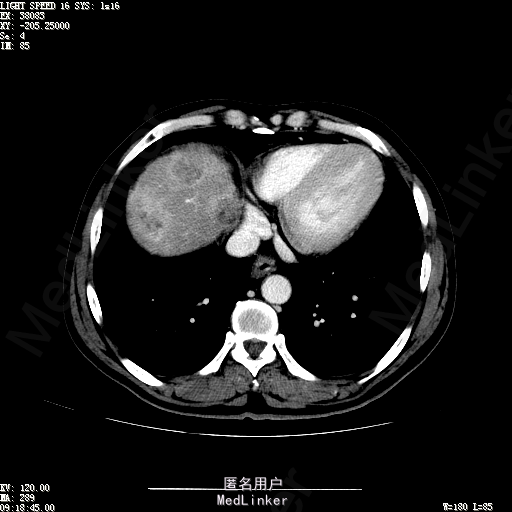

查体:生命体征平稳,神志清晰,发育正常,营养中等,体位自如,表情安静,无面容,配合检查合作。皮肤粘膜颜色正常,腹型平坦,无腹壁静脉曲张,未见胃肠型及蠕动波,无瘢痕,脐部正常。触诊:无压痛,无反跳痛,无腹肌紧张,无腹部包块。肝未触及,Murphy征阴性,脾未触及,肾未触及,无移动性浊音。 化验回报:血细胞分析(五分类):*白细胞计数 4.6 10^9/L、红细胞计数 4.27 10^12/L、血小板计数 100.0 10^9/L、血红蛋白 145 g/L、中性粒细胞百分比 68.6 %,*葡萄糖测定:葡萄糖 5.99 mmol/L,血清离子测定:*钾 4.46 mmol/L、钠 143.5 mmol/L,肾功能检测:*尿素 6.86 mmol/L、肌酐 84.2 umol/L,凝血五项:凝血酶原时间 10.7 秒、凝血酶原百分活动度 93.3 %,乙肝六项:乙型肝炎病毒表面抗原 阳性(+) 、乙型肝炎病毒e抗体 阳性(+) 、乙型肝炎病毒核心抗体 阳性(+) ,甲胎蛋白测定:甲胎蛋白 7146.00 ng/mL,ALT23U/L,AST42U/L CT检查如下图

诊断:乙肝肝硬化 静止性 代偿期 原发性肝癌 2型糖尿病 高血压病 下肢动脉闭塞征 诊断依据:1.有明确乙肝肝硬化病史 2.肝区隐痛,于外院发现肝占位,我院诊断肝癌,已行TACE治疗 3.查体:有肝掌 4.既往影像学提示肝内占位 处置:血管介入治疗:患者平卧位,以左侧肘窝为中心常规消毒、铺巾、利多卡因局麻。超声引导下,于肘横纹上方1厘米处确定皮肤穿刺点,改良Seldinger法逆行穿刺左侧肱动脉成功,置入5F血管鞘。沿导丝送入Cobra C2导管,送入降主动脉,将管头送入腹腔干,进一步送至肝固有动脉。造影见肝内广泛弥漫肿瘤染色,以右叶为主。以微导管超选肝右动脉,造影明确为肿瘤供血动脉,注入碘化油5毫升。退出微导管,经C2管注入奥沙利铂100毫克。退出C2管。拔出血管鞘,局部压迫10分钟。加压包扎。患者送返病房。